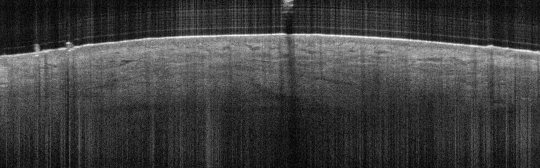

VA9: Left Forearm, Adjacent Normal